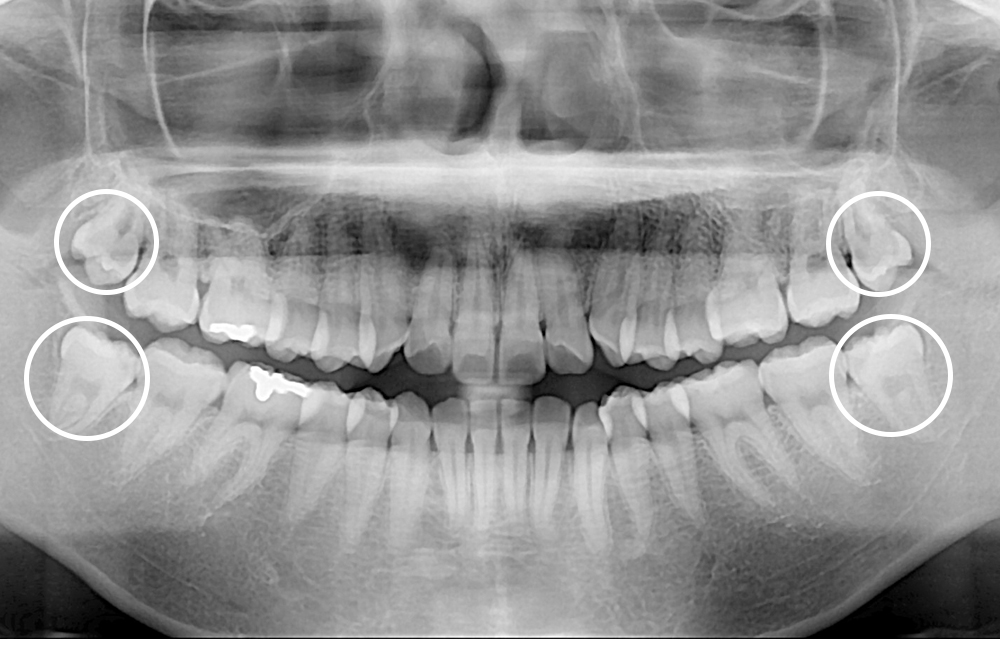

[사랑니] 매복 사랑니 발치

치료후 : 2020-08-17

세종치과는 구강악안면외과학 박사이신 원장님이 발치하는 치과입니다.